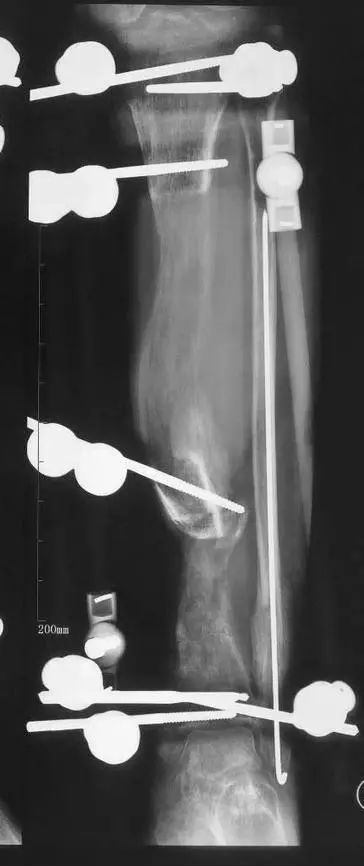

最后一个病例

(网友提供)最后的病例是伤后40天由外地转来。开放骨折外固定架固定,骨坏死外露,用连珠和双氧水冲洗。入院时还存在足下垂,腓神经损伤、胫后动脉损伤。

• 接收该患者后第一次手术  清除病灶去除死骨27cm

• 抗生素骨水泥填塞。远端整块水泥包裹外露骨质,近端连珠以便骨搬移

• 钢丝克氏针张力牵拉皮肤,缩小创面

• 5天后下地部分负重走路

• 联合骨牵引纠正足下垂,5天后足下垂纠正后去除跟骨骨牵引针,保留胫跖骨牵引维持足于功能位。

• 而后行骨搬移、半开放植骨(如下)